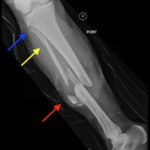

Plain film shows severely comminuted and displaced mid tibia/fibula fractures of bilateral lower extremities (red arrows) and comminuted right fibular head (blue arrow) and proximal shaft fracture (yellow arrow).